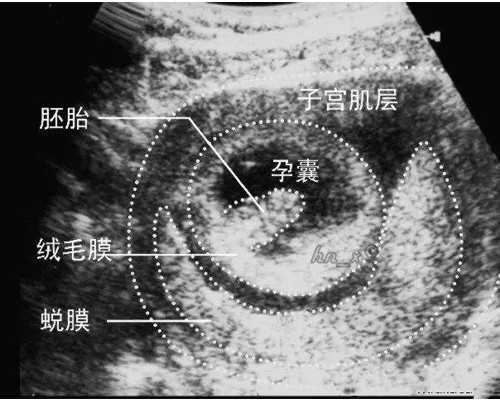

首先孕妈需要去当地的妇幼保健院做B超检查自己是否妊娠期满7周,胚芽长度有没有达到10mm,当满足这些条件的时候就可以提前1-2天联系香港验血提前预约,可以采取电话预约也可以通过微信预约。预约时候需要提供孕妈的姓名电话以及到港时间等。那么孕妈去往香港的时候要准备哪些材料呢?

第二:检查自身条件满足孕期满七周以及胚芽长度达到10mm,最好能够在办理签证的时候去做B超并有医生签名,因为去香港抽血化验前会有专门的医生对接孕妈,了解孕妈身体状况,看是否能够做抽血化验,B超单就是很好的证明。

2、宝妈的胎儿胚芽不能超过十毫米;